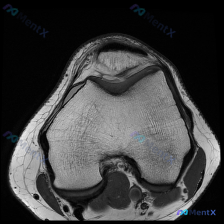

最近碰到一个有意思的病例,患者主诉考虑膝关节软骨异常,只提供了一张髌股关节层面的T1加权轴位MRI,整理一下分析思路和大家讨论。 病例基本信息 - 核心问题:评估影像是否存在软骨异常 - 影像资料:单张膝关节髌股关节层面T1加权轴位MRI 影像读片结果 先给大家整理读片的核心发现: 1. 骨骼结构:...

刚看到这个有意思的影像病例,整理一下完整资料和分析思路给大家参考。 病例基本信息 这是一张膝关节MRI T1加权轴位扫描影像,核心问题是:临床提示存在「软骨异常」,需要解读影像表现并分析原因。 影像客观评估结果 先给大家说客观的影像发现: 1. 骨性结构:股骨远端滑车、髌骨的骨皮质完整,松质骨髓信号...

今天看到一个很有代表性的读片问题,整理一下思路分享给大家。 病例/问题背景 问题:针对一张标注怀疑「软骨异常」的膝盖MRI T1加权轴位图像,描述可见的视觉表现。 --- 影像基础信息 图像为单张膝关节水平面T1加权成像(T1WI),这个序列的基本信号特点是:骨髓、皮下脂肪呈高信号(亮),肌肉呈中等...

刚整理了一个很有讨论价值的读片病例,先给大家把信息理清楚: 病例基本信息 临床提示:怀疑膝关节软骨异常,提供单张膝盖MRI-T1加权轴位图像读片 影像读片结果 我们先逐层评估解剖结构: 1. 骨骼与骨髓:股骨远端、髌骨皮质完整,无中断;骨髓腔内T1高信号,符合正常脂肪骨髓,没有局灶低信号区 2. 关...